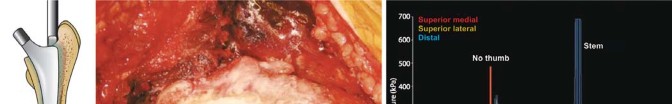

استبدال مفصل الورك الكلي بالإسمنت هو إجراء جراحي ناجح للغاية يعالج آلام الورك الشديدة ويستعيد وظيفة المفصل. يتضمن تثبيت غرسة الفخذ باستخدام إسمنت عظمي خاص، وتعتمد نتائجه الممتازة على دقة الخطوات الجراحية لضمان تثبيت قوي ومستقر يدوم طويلاً.

تقنية الإسمنت للفخذ، التي تُعد محور حديثنا، هي طريقة راسخة لتثبيت المكون الفخذي (الجزء الذي يتم إدخاله في عظم الفخذ) من المفصل الصناعي باستخدام إسمنت عظمي خاص. يضمن هذا الإسمنت استقرارًا فوريًا وقوة تحمل عالية، مما يجعله خيارًا ممتازًا للعديد من المرضى، وخاصة كبار السن وذوي العظام الضعيفة. ستكتشف في هذا الدليل لماذا تُعد هذه التقنية خيارًا موثوقًا به، وكيف يمكن أن تُحدث فرقًا حقيقيًا في حياتك.